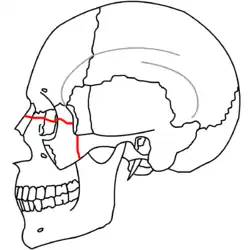

Traditionally, Le Fort described three types of fractures. All three fractures involve the nasal septum and the pterygoid plates.[2]

- The Le Fort II fracture (pyramidal fracture) includes a fracture line from one of the lateral vertical buttresses across the maxillary bone, extending into the inferior orbital rim and crossing the midline (either through the nasal root or nasal bones).[5] The defining feature of this fracture pattern is involvement of the inferior orbital rim.[5] When viewed from the front, this fracture is classically shaped like a pyramid.

- The Le Fort III fracture (transverse fracture) occurs at the level of the skull base, resulting in complete craniofacial separation of the midface from the base of the skull.[2][3] The fracture line extends through the zygomatic arch, the pterygoid plates, the lateral and medial orbital walls, the nasal bones, and the nasal septum.[2][5] The salient feature of these fractures is that they invariably involve the zygomatic arch, or cheek bone.[5] These are the most extensive of the Le Fort fractures and often require open surgical intervention.[3]